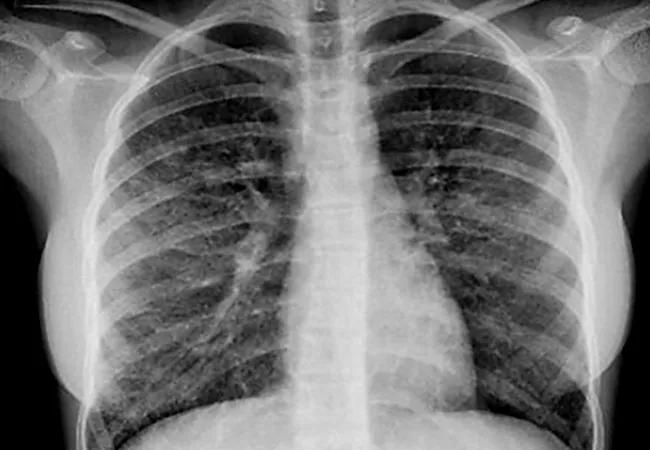

Chest x-ray adolescent vaping injury

Although e-cigarettes were beneficial in achieving abstinence, the concern is that individuals continued to use them. It is not clear whether e-cigarettes truly reduce harm as they are not as safe as they are promoted to be. While nicotine inhalation with e-cigarettes is thought to release fewer toxic by-products than combustible cigarettes, there are concerns regarding their safety. Carcinogens and toxins have been found in the liquid used for vaporization and in the aerosols emitted, and e-cigarettes have been associated with an outbreak of cases of acute lung injury that caused hospitalizations and even deaths.

The long-term consequences are unknown, but several studies have shown the potential of e-cigarettes to cause chronic lung and heart disease and to increase the risk of infection and of cancer.